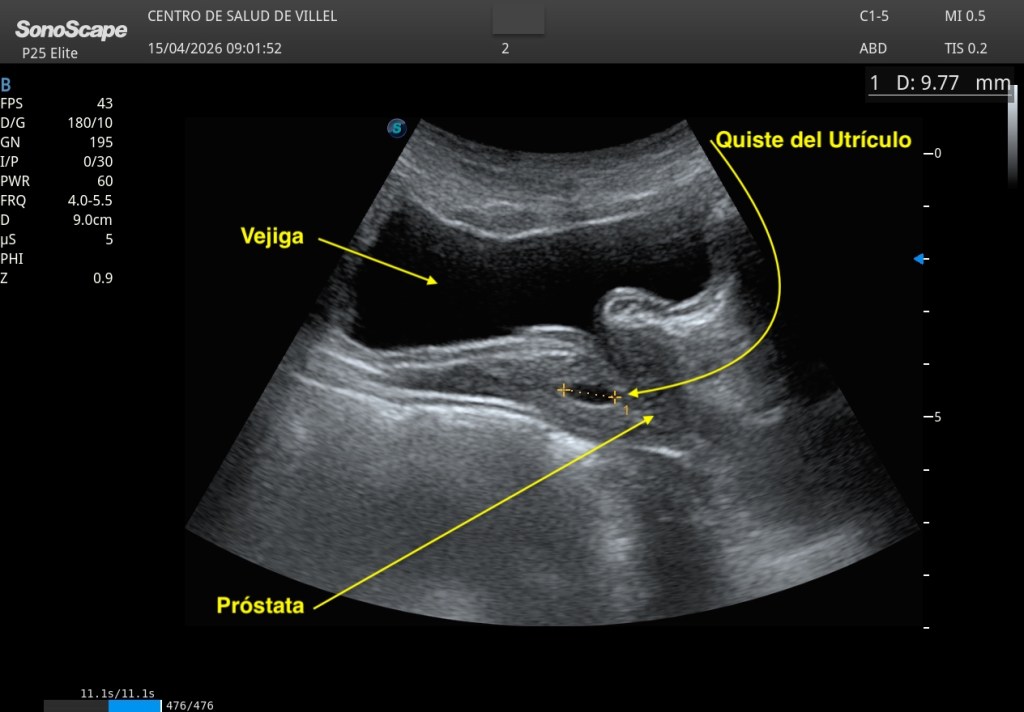

En un paciente joven, de unos 20 años, se identificó una pequeña imagen anecoica, central, localizada en la próstata, de aproximadamente 5 a 10 milímetros en su eje longitudinal mayor, bien delimitada, de apariencia quística y sin signos ecográficos de complejidad. Una imagen pequeña, sutil incluso, pero con una localización muy característica. Aquí te dejo las imágenes clave:

Ante una lesión quística medial prostática en un paciente de esta edad, inevitablemente surge la sospecha y hay que consultar con el radiólogo responsable. Se documenta muy bien, y se comenta con el radiólogo, como he mencionado previamente.